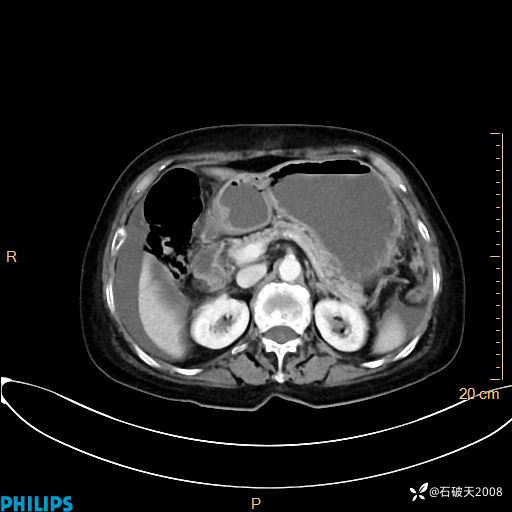

动脉期